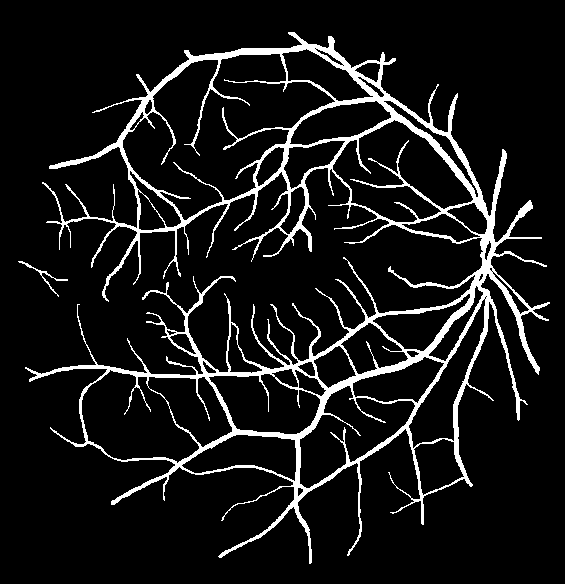

VI-A Retinal Artery and Vein Segmentation

As reported in Table IV, we compared the SegRAVIR model against competing deep learning-based segmentation approaches on the RAVIR dataset. Evidently, SegRAVIR outperforms these methods as judged by all metrics for artery and vein classes with a healthy margin. In terms of Dice score, SegRAVIR outperforms CE-NET, IterNet and AG-Net by , and for artery segmentation and by , and for vein segmentation, respectively. Fig. 4 presents a qualitative comparison of the semantic segmentation outputs of SegRAVIR, CE-Net, and U-Net. Specifically, SegRAVIR yields more accurate vessel topology (i.e., thickness and orientation) segmentation with higher pixel-wise classification accuracy.

Table V presents quantitative performance benchmarks of SegRAVIR and other competing approaches for retinal artery and vein classification on the RITE dataset [11]. SegRAVIR outperforms previous state-of-the-art approaches in terms of accuracy, sensitivity, and specificity. Fig. 5 provides a qualitative comparison between segmentation outputs of SegRAVIR and the method of Hemelings et al. [40] on the RITE test set.